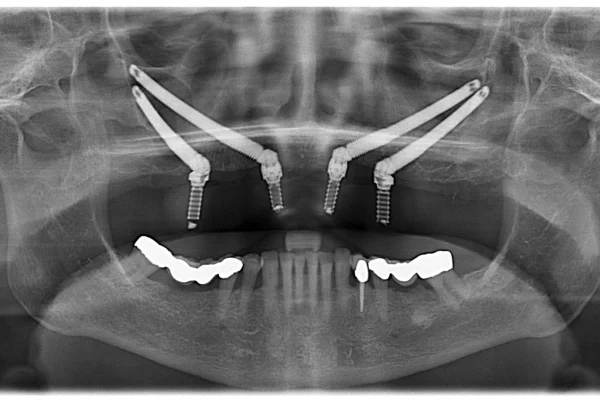

At Dentale Albania, we believe dental care abroad should be as stress-free as possible. That’s why we’re expanding our service offerings to include comprehensive travel packages that go beyond dentistry. From airport pickup and 4-star accommodation to local tours, our packages are crafted to give you not just a new smile — but an unforgettable Albanian experience. Whether you’re here for implants, veneers, or full-arch restorations, we handle everything so you can focus on your transformation.